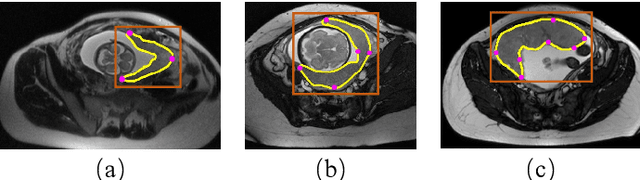

Abstract:Segmentation of organs or lesions from medical images plays an essential role in many clinical applications such as diagnosis and treatment planning. Though Convolutional Neural Networks (CNN) have achieved the state-of-the-art performance for automatic segmentation, they are often limited by the lack of clinically acceptable accuracy and robustness in complex cases. Therefore, interactive segmentation is a practical alternative to these methods. However, traditional interactive segmentation methods require a large amount of user interactions, and recently proposed CNN-based interactive segmentation methods are limited by poor performance on previously unseen objects. To solve these problems, we propose a novel deep learning-based interactive segmentation method that not only has high efficiency due to only requiring clicks as user inputs but also generalizes well to a range of previously unseen objects. Specifically, we first encode user-provided interior margin points via our proposed exponentialized geodesic distance that enables a CNN to achieve a good initial segmentation result of both previously seen and unseen objects, then we use a novel information fusion method that combines the initial segmentation with only few additional user clicks to efficiently obtain a refined segmentation. We validated our proposed framework through extensive experiments on 2D and 3D medical image segmentation tasks with a wide range of previous unseen objects that were not present in the training set. Experimental results showed that our proposed framework 1) achieves accurate results with fewer user interactions and less time compared with state-of-the-art interactive frameworks and 2) generalizes well to previously unseen objects.

Abstract:Convolutional neural networks (CNNs) have achieved state-of-the-art performance for automatic medical image segmentation. However, they have not demonstrated sufficiently accurate and robust results for clinical use. In addition, they are limited by the lack of image-specific adaptation and the lack of generalizability to previously unseen object classes. To address these problems, we propose a novel deep learning-based framework for interactive segmentation by incorporating CNNs into a bounding box and scribble-based segmentation pipeline. We propose image-specific fine-tuning to make a CNN model adaptive to a specific test image, which can be either unsupervised (without additional user interactions) or supervised (with additional scribbles). We also propose a weighted loss function considering network and interaction-based uncertainty for the fine-tuning. We applied this framework to two applications: 2D segmentation of multiple organs from fetal MR slices, where only two types of these organs were annotated for training; and 3D segmentation of brain tumor core (excluding edema) and whole brain tumor (including edema) from different MR sequences, where only tumor cores in one MR sequence were annotated for training. Experimental results show that 1) our model is more robust to segment previously unseen objects than state-of-the-art CNNs; 2) image-specific fine-tuning with the proposed weighted loss function significantly improves segmentation accuracy; and 3) our method leads to accurate results with fewer user interactions and less user time than traditional interactive segmentation methods.